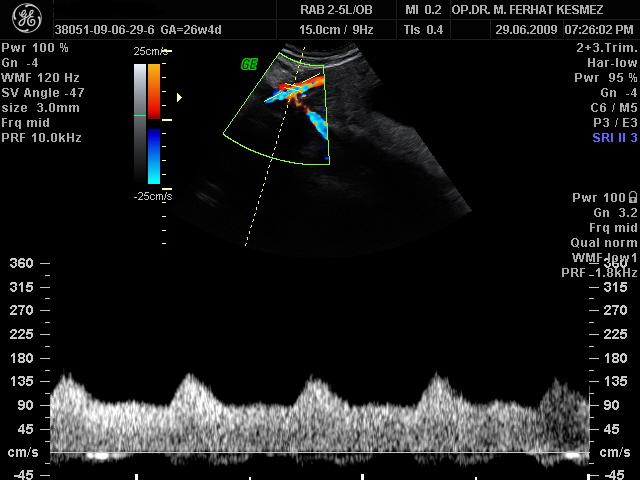

Ultrason Ölçümleri